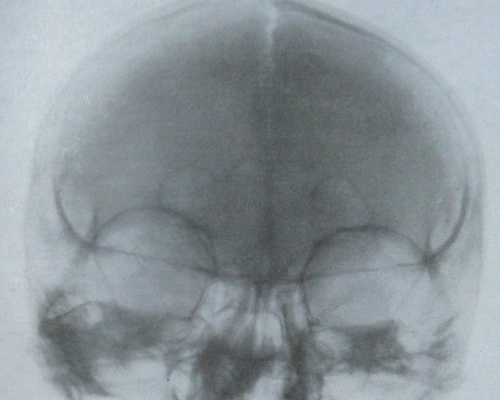

Рентгенография небного шва: Медицинские исследования и диагностика